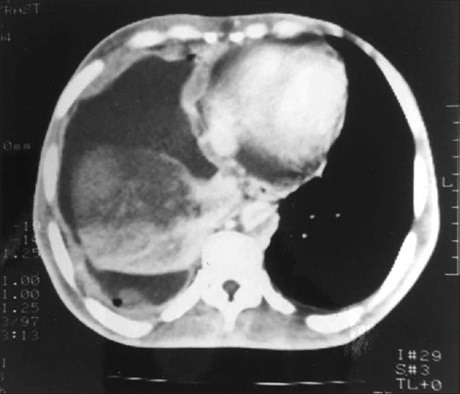

Background: Whitening out of half of the lung field on a chest X‑ray is known as opacification of a hemithorax, and its presence usually indicates a significant disease in a patient. This study was done with an aim of finding different etiologies as the cause of complete opacification of a hemithorax on chest radiograph.

Materials and Methods: An observational cross‑sectional study of patients whose chest radiograph had opaque hemithorax was included and after clinical laboratory and advanced radiological ‑ ultrasonography (USG) and computed tomography investigation of these patients the diagnosis responsible for the complete opacification of half the lung field in chest X‑ray was recorded.

Results: Atotal of 30 patients (23 males and 7 females) were enrolled for the study. Out of the 30 patients, 17 involved the left while 13 involved the right hemithorax. Fifteen patients had clear pleural effusion, 13 patients had mass with pleural

effusion and 2 patients were postpneumonectomy cases. Mediastinal shift to contralateral side was seen in 18 out of 30 patients having opaque hemithorax. Eleven patients have biochemical features of tuberculosis. All 13 patients with mass and effusion were confirmed to have malignancy on histology. USG could detect malignancy in only ten cases. Chest pain was most frequent symptom and smoking or tobacco habit was associated with 14 cases.

Conclusion: Plain pleural effusion was the most common etiology of opaque hemithorax in our study followed by mass with effusion. Among other rarer causes, only pneumonectomy was seen. For other rare causes that may present as opaque hemithorax larger study may be done.